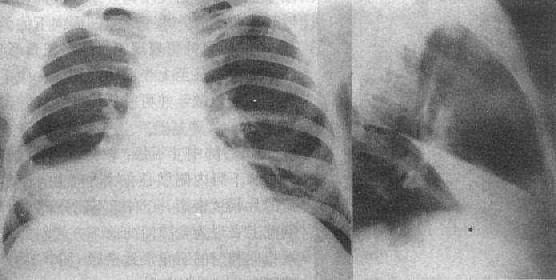

2)右肺中叶不张:较为常见,后前位表现为右肺下野内侧靠心右缘现上界清楚下界模糊的片状致密影,心右缘不能分辨(图3-1-9)。侧位上表现为自肺门向前下方倾斜的带状或尖端指向肺门的三角形致密影(图3-1-9)。上、下叶可有代偿性肺气肿。

图3-1-9 右肺中叶肺不张(正、侧位)